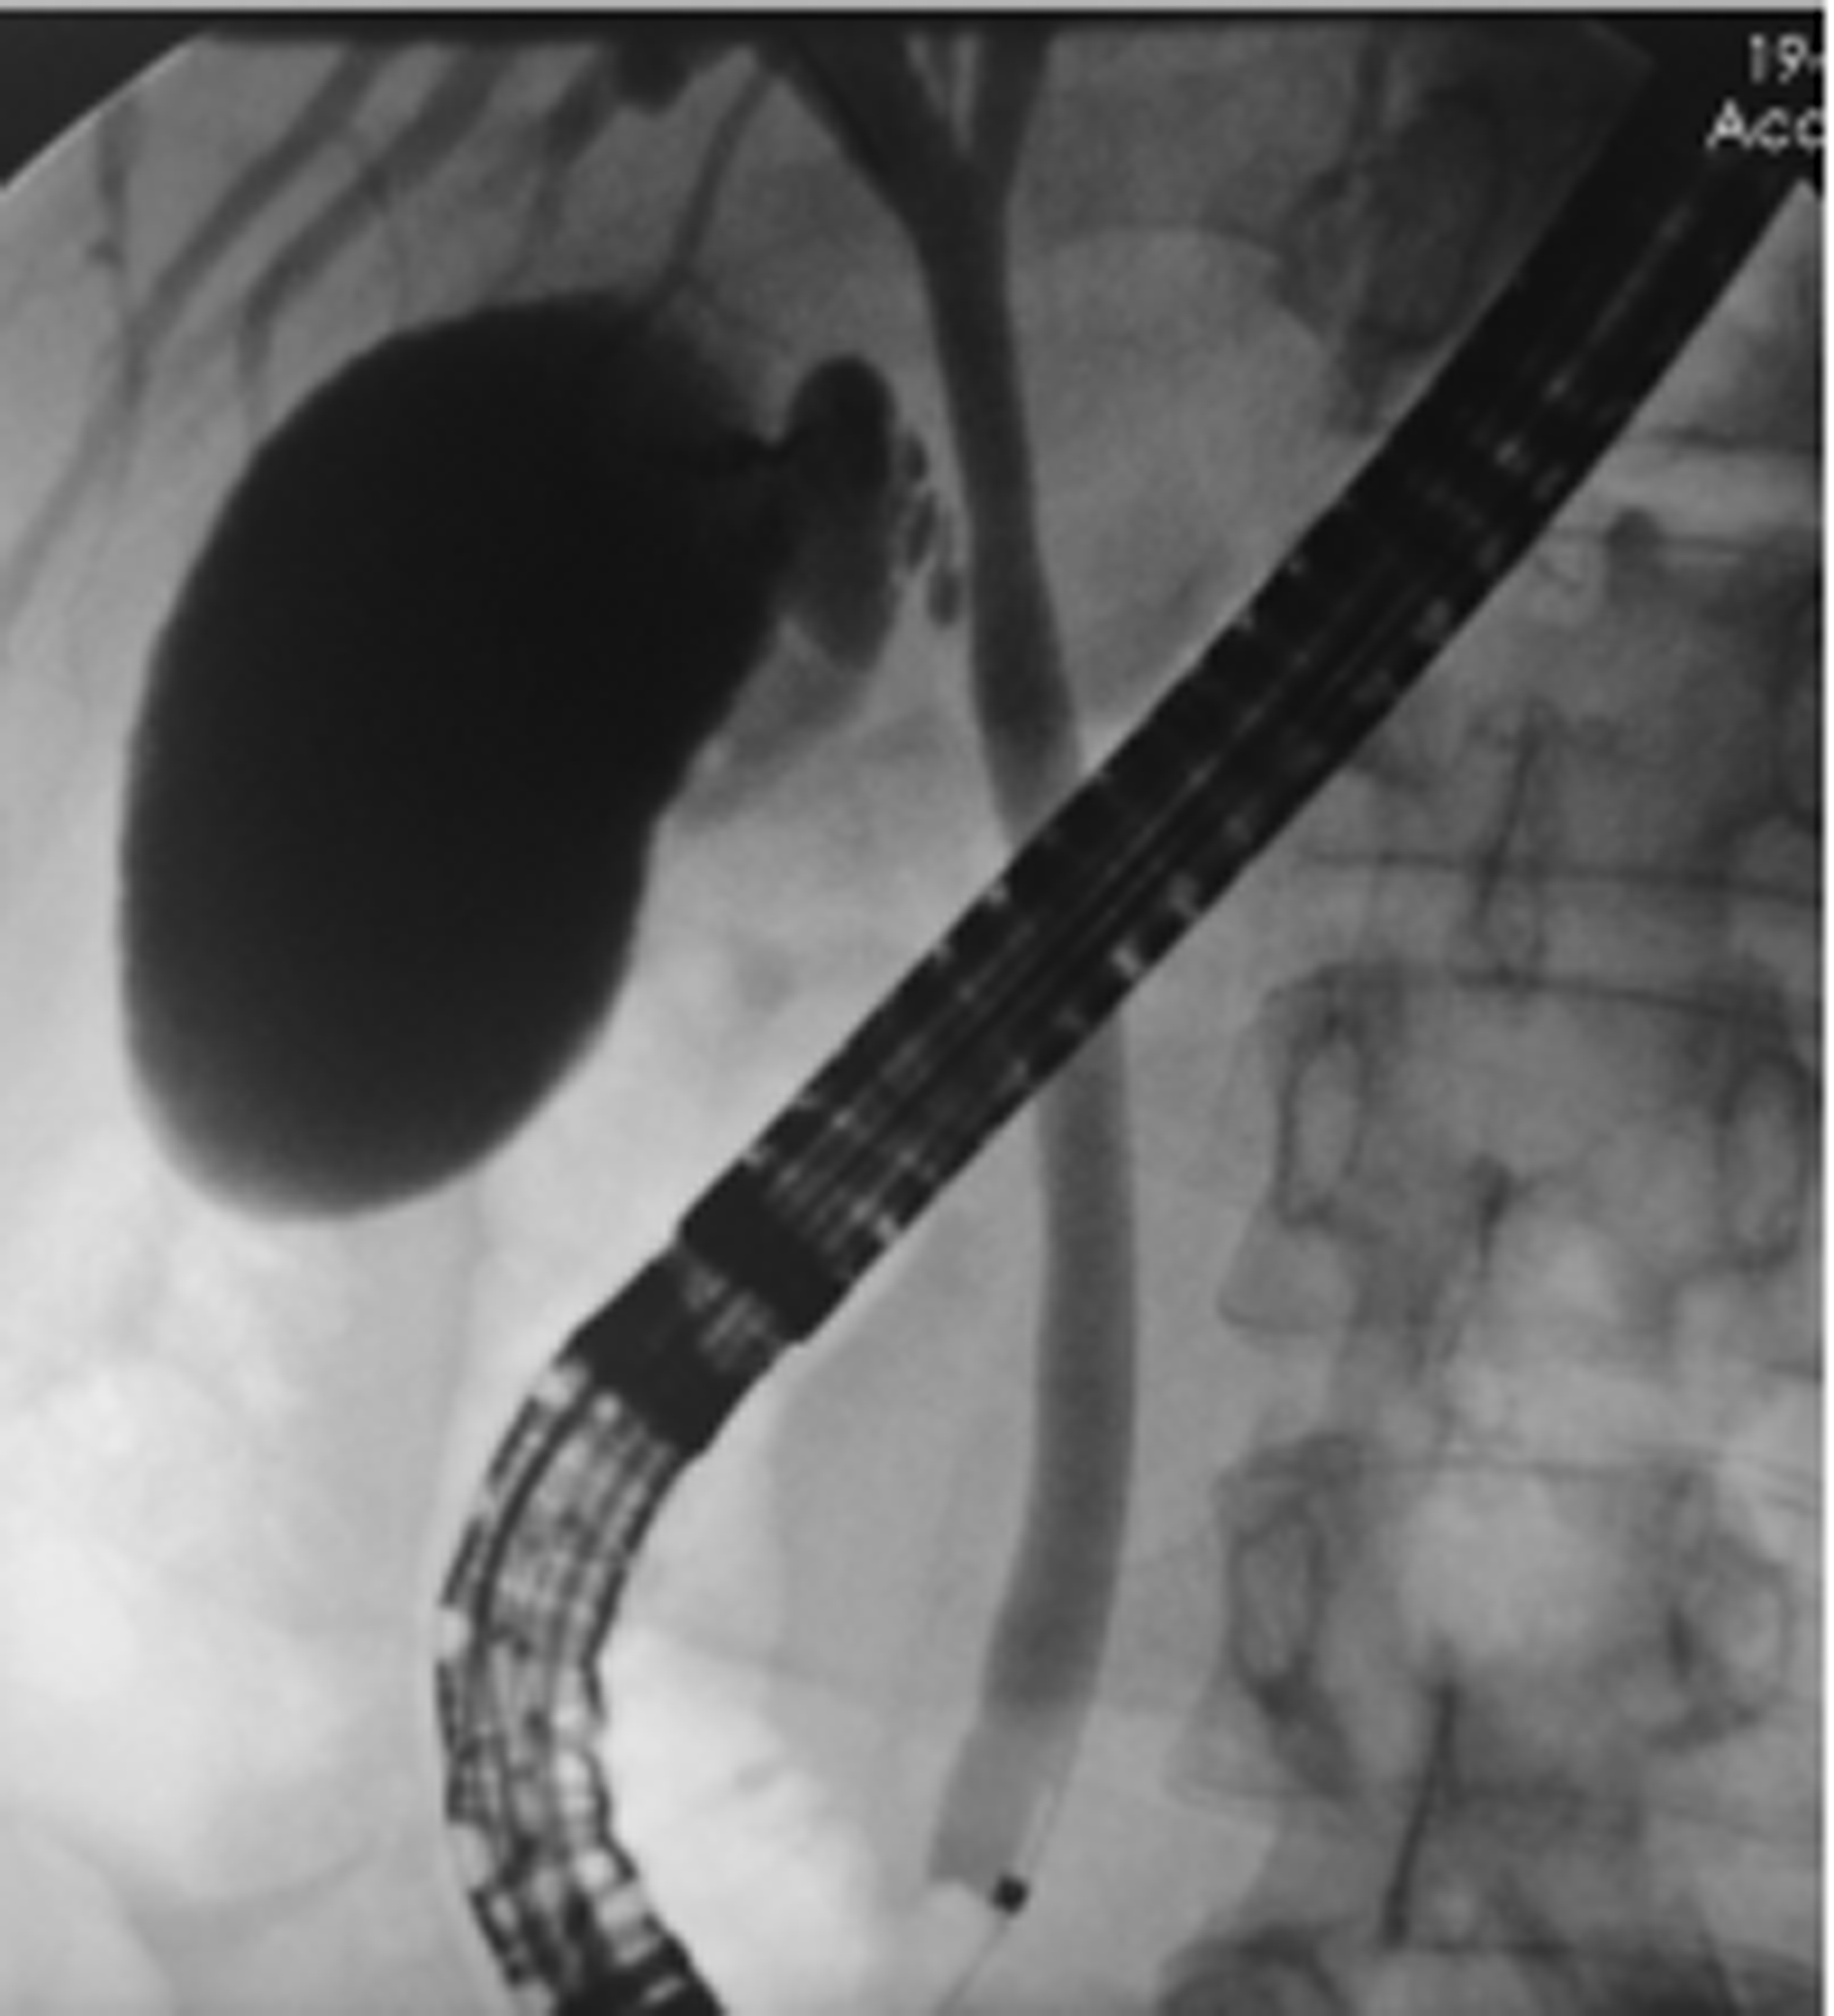

胰管结石治疗方案的选择分析与比较

摘要:

目的  收集并对比分析内镜逆行胰胆管造影(ERCP)、腹腔镜术和开腹手术三种方案治疗胰管结石(PDS)患者的临床资料及治疗效果,总结PDS治疗方案选择的经验,进一步研究探讨可行的使患者获益最大化、最优化的治疗方案。  方法  回顾性分析2014年6月—2018年12月海军军医大学附属公利医院治疗的131例PDS患者的临床资料。根据手术情况分为3组:ERCP组69例,腔镜组32例,开腹组30例。监测3组患者手术前后相关指标的变化;进一步对比分析腔镜组和开腹组的手术疗效。正态分布的计量资料两组间比较采用独立样本t检验;多组间比较采用单因素方差分析,进一步两两比较采用LSD-t检验或SNK-q检验。偏态分布的计量资料两组间比较采用Mann-Whitney U检验,多组间比较采用Kruskal-Wallis H检验。手术前后相关指标差异比较采用重复测量资料的方差分析和Friedman检验。计数资料组间比较采用χ2检验。  结果  131例PDS患者中Ⅰ型40例、Ⅱ型76例、Ⅲ型15例。腔镜组与开腹组主要手术方式的病例数比较差异无统计学意义(χ2=1.93,P>0.05)。腔镜组和开腹组血WBC、CRP、PCT、HOMA-IR在手术前后的动态变化存在明显差异(F=24.68、χ2=227.66、F=45.37、F=106.71,P值均<0.05)。腔镜组手术时长、术中出血量、术后首次排气时间、术后止痛药物应用频次、腹腔引流管拔除时间、术后近期并发症、术后平均住院时长等观察指标均较开腹组明显减少/缩短(t=-4.80、t=-9.43、Z=-6.78、t=-11.59、Z=-6.77、χ2=9.24、t=-3.60,P值均<0.05)。ERCP组、腔镜组、开腹组术后近期并发症发生率分别为24.64%、28.13%、66.67%,差异有统计学意义(χ2=17.12,P<0.05);ERCP组及腔镜组术后近期并发症发生率均显著低于开腹组(χ2值分别为15.78、9.24,P值分别为<0.05、0.02)。ERCP组、腔镜组、开腹组治疗有效率分别为91.30%、93.75%、73.33%,3组间有效率差异有统计学意义(χ2=7.70,P=0.02),ERCP组及腔镜组有效率均好于开腹组(χ2值分别为5.56、4.77,P值分别为0.02、0.03)。  结论  ERCP为临床微创治疗部分Ⅰ、Ⅱ型PDS的首选治疗方法,安全有效、严重并发症少。外科手术是治疗复杂型PDS的重要手段,但技术复杂、操作难度大。腹腔镜术较开腹术创伤小、严重并发症少,腹痛缓解率高,可以显著减少手术时长、降低术中出血量及缩短术后平均住院时长。针对复杂型PDS宜优先选择腹腔镜术治疗。